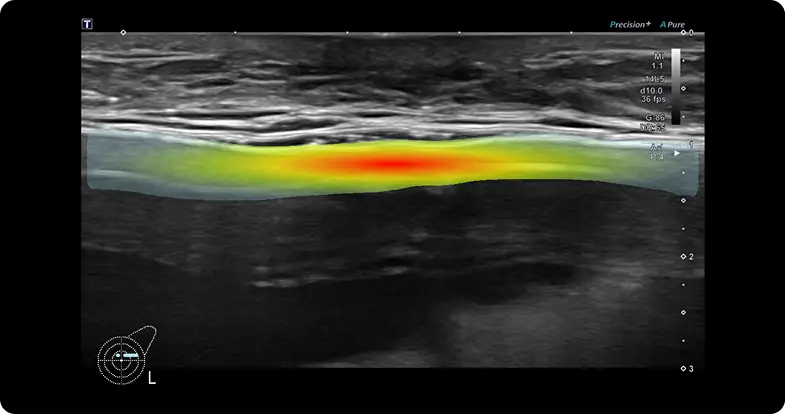

Precise Breast-Implant Diagnosis with ROI MarkingPrecise Breast-Implant Diagnosis with ROI Marking W Expert’s advanced segmentation algorithm highlights the region of interest (ROI) in each ultrasound frame. Through architecture refinements, optimized preprocessing, and fine-tuning, it achieves precise pixel-level delineation, giving surgeons and radiologists clear visual guidance for early detection, objective measurement, and efficient treatment planning.

AI Algorithms for Accurate DiagnosisFine-tuned on over 2.3 million breast-implant ultrasound images, our deep-learning engine delivers clinically proven performance with > 95 % accuracy and > 97 % specificity for key complications such as rupture and capsular change. This validated binary classification provides fast, reproducible results that help clinicians make confident, evidence-based decisions.